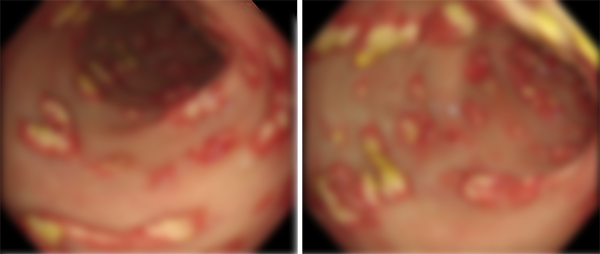

看着老郑痛苦的样子,我迅速接过他的化验报告和肠镜检查结果,仔细地研究起来。化验报告中并没有什么特别的异常,但当我看到肠镜检查图片的那一刻,一下子豁然开朗。直觉告诉我,这不是简单的结肠炎。

我微笑着对老郑说:“老郑,别担心,我认为您的情况很可能是伪膜性肠炎,不需要再做其他的检查。”老郑听了我的话,原本黯淡的眼神里闪现出了一丝希望的光亮。他的嘴角也微微上扬,仿佛抓住了救命稻草一般。

那老郑得的伪膜性肠炎到底是个啥呢?为什么用左氧氟沙星越来越重呢?我来给大家简单说说。伪膜性肠炎是艰难梭菌感染引起的急性肠炎,和免疫力低下有关系。通常情况下,患者在使用广谱抗生素(如左氧氟沙星)后,会破坏肠道得正常菌群,此时艰难梭菌就会趁虚而入,导致炎症,并在肠壁上形成类似“膜”的黄色覆盖物。